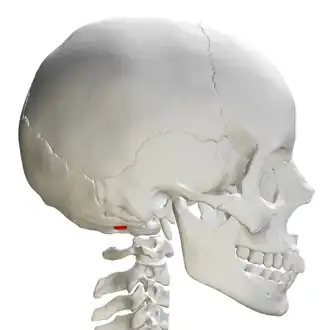

![]() Skull and cervical vertebra. Position of condyloid fossa shown in red. | |

Behind either condyle of the lateral parts of occipital bone is a depression, the condyloid fossa (or condylar fossa), which receives the posterior margin of the superior facet of the atlas when the head is bent backward; the floor of this fossa is sometimes perforated by the condyloid canal, through which an emissary vein passes from the transverse sinus.

Human skull seen from below. Position of condyloid fossa shown in red. -

Skull and cervical vertebra. Position of condyloid fossa shown in red. -